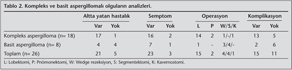

Radyolojik Bulgular ve Tan?

Belcher ve Plummer'?n radyolojik s?n?fland?rmas? g?z ?n?ne al?narak yap?lan s?n?fland?rmada 8 (%30) olgu? basit, 18 (%70) olgu kompleks aspergilloma olarak belirlendi (9) (Tablo 2). On yedi olgunun preoperatif aspergilloma tan?s? radyolojik g?r?n?mlerindeki karakteristik yar?m ay ?eklinde radyol?sens alanla ?evrili mantar topu (Monad's sign) g?z ?n?ne al?narak konmu?tu. Geriye kalan dokuz olgunun tan?s? patoloji piyesiyle konuldu. Bu olgular?n ??? masif hemoptizi nedeniyle opere edilen, ??? semptomu olmay?p eksplorasyon uygulanan, ??? de ba?ka tan?larla (biri haraplanm?? akci?er, biri bron?ektazi, biri de skuam?z h?creli akci?er karsinomu) operasyona al?nan olgulard?.

Cerrahi Endikasyonlar, Operasyon Tipi ve Operatif Bulgular

Olgular?n 15'ine hemoptizi (???ne masif hemoptizi nedeniyle hayat kurtar?c?), ???ne tan?sal ama?l?, ???ne di?er akci?er hastal?klar? (biri haraplanm?? akci?er, biri bron?ektazi, biri de skuam?z h?creli akci?er karsinomu), be?ine de di?er yak?nmalar nedeniyle posterolateral torakotomi uyguland?. En s?k uygulanan operasyon tipi lobektomiydi (%57.6). Lobektomi uygulanan olgulardan ikisi acil olarak torakotomiye al?nan olgulard?. ?? olguya lobektomiye ek olarak segmentektomi eklenmi?ti. Geri kalan 11 olgunun 4 (%15.3)'?ne segmentektomi, 4 (%15.3)'?ne wedge rezeksiyon, birine acil olmak ?zere 2 (%7.6)'sine pn?monektomi, 1 (%3.8)'ine de intratorasik ekstraplevral alanda yer almas? nedeniyle kavernostomi ve fungus topu eksizyonu uygulanm??t?. Basit aspergillomal? olgulara s?kl?kla segmentektomi/wedge rezeksiyon gibi parankim koruyucu operasyonlar uygulanm??t?. Lobektomi uygulanan olgular?n sadece biri basit aspergilloma tan?l?yd?. Kompleks aspergillomal? olgulara istatistiksel olarak daha fazla lobektomi veya pn?monektomi uyguland??? izlendi (Tablo 2). Olgular?n %20'sine adezyonlar?n ayr?lmas? s?ras?nda plevro-parankimal kanaman?n olu?mas? ?zerine yer yer ekstraplevral diseksiyon uygulanm??t?.